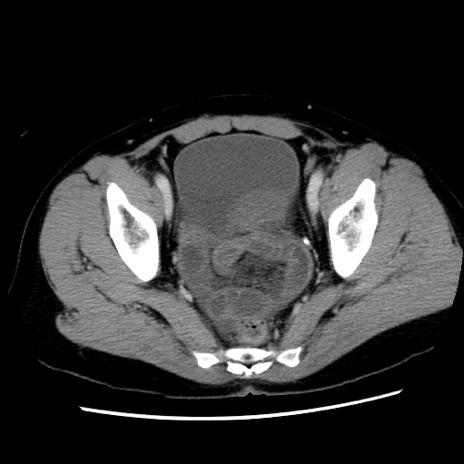

症例10(横断像)

【症例】 50歳代女性

【主訴】 腹痛

【現病歴】前日生レバーを食べた。今朝に排便あり。 昼前に突然発症の腹痛を生じ、当院救急外来を受診した。

【既往歴】 子宮筋腫にてで子宮全摘後

【身体所見】 意識清明、腹部:平坦、軟、下腹部やや左を中心に圧痛・反跳痛あり、筋性防御あり

【データ】WBC 7800、CRP 0.07